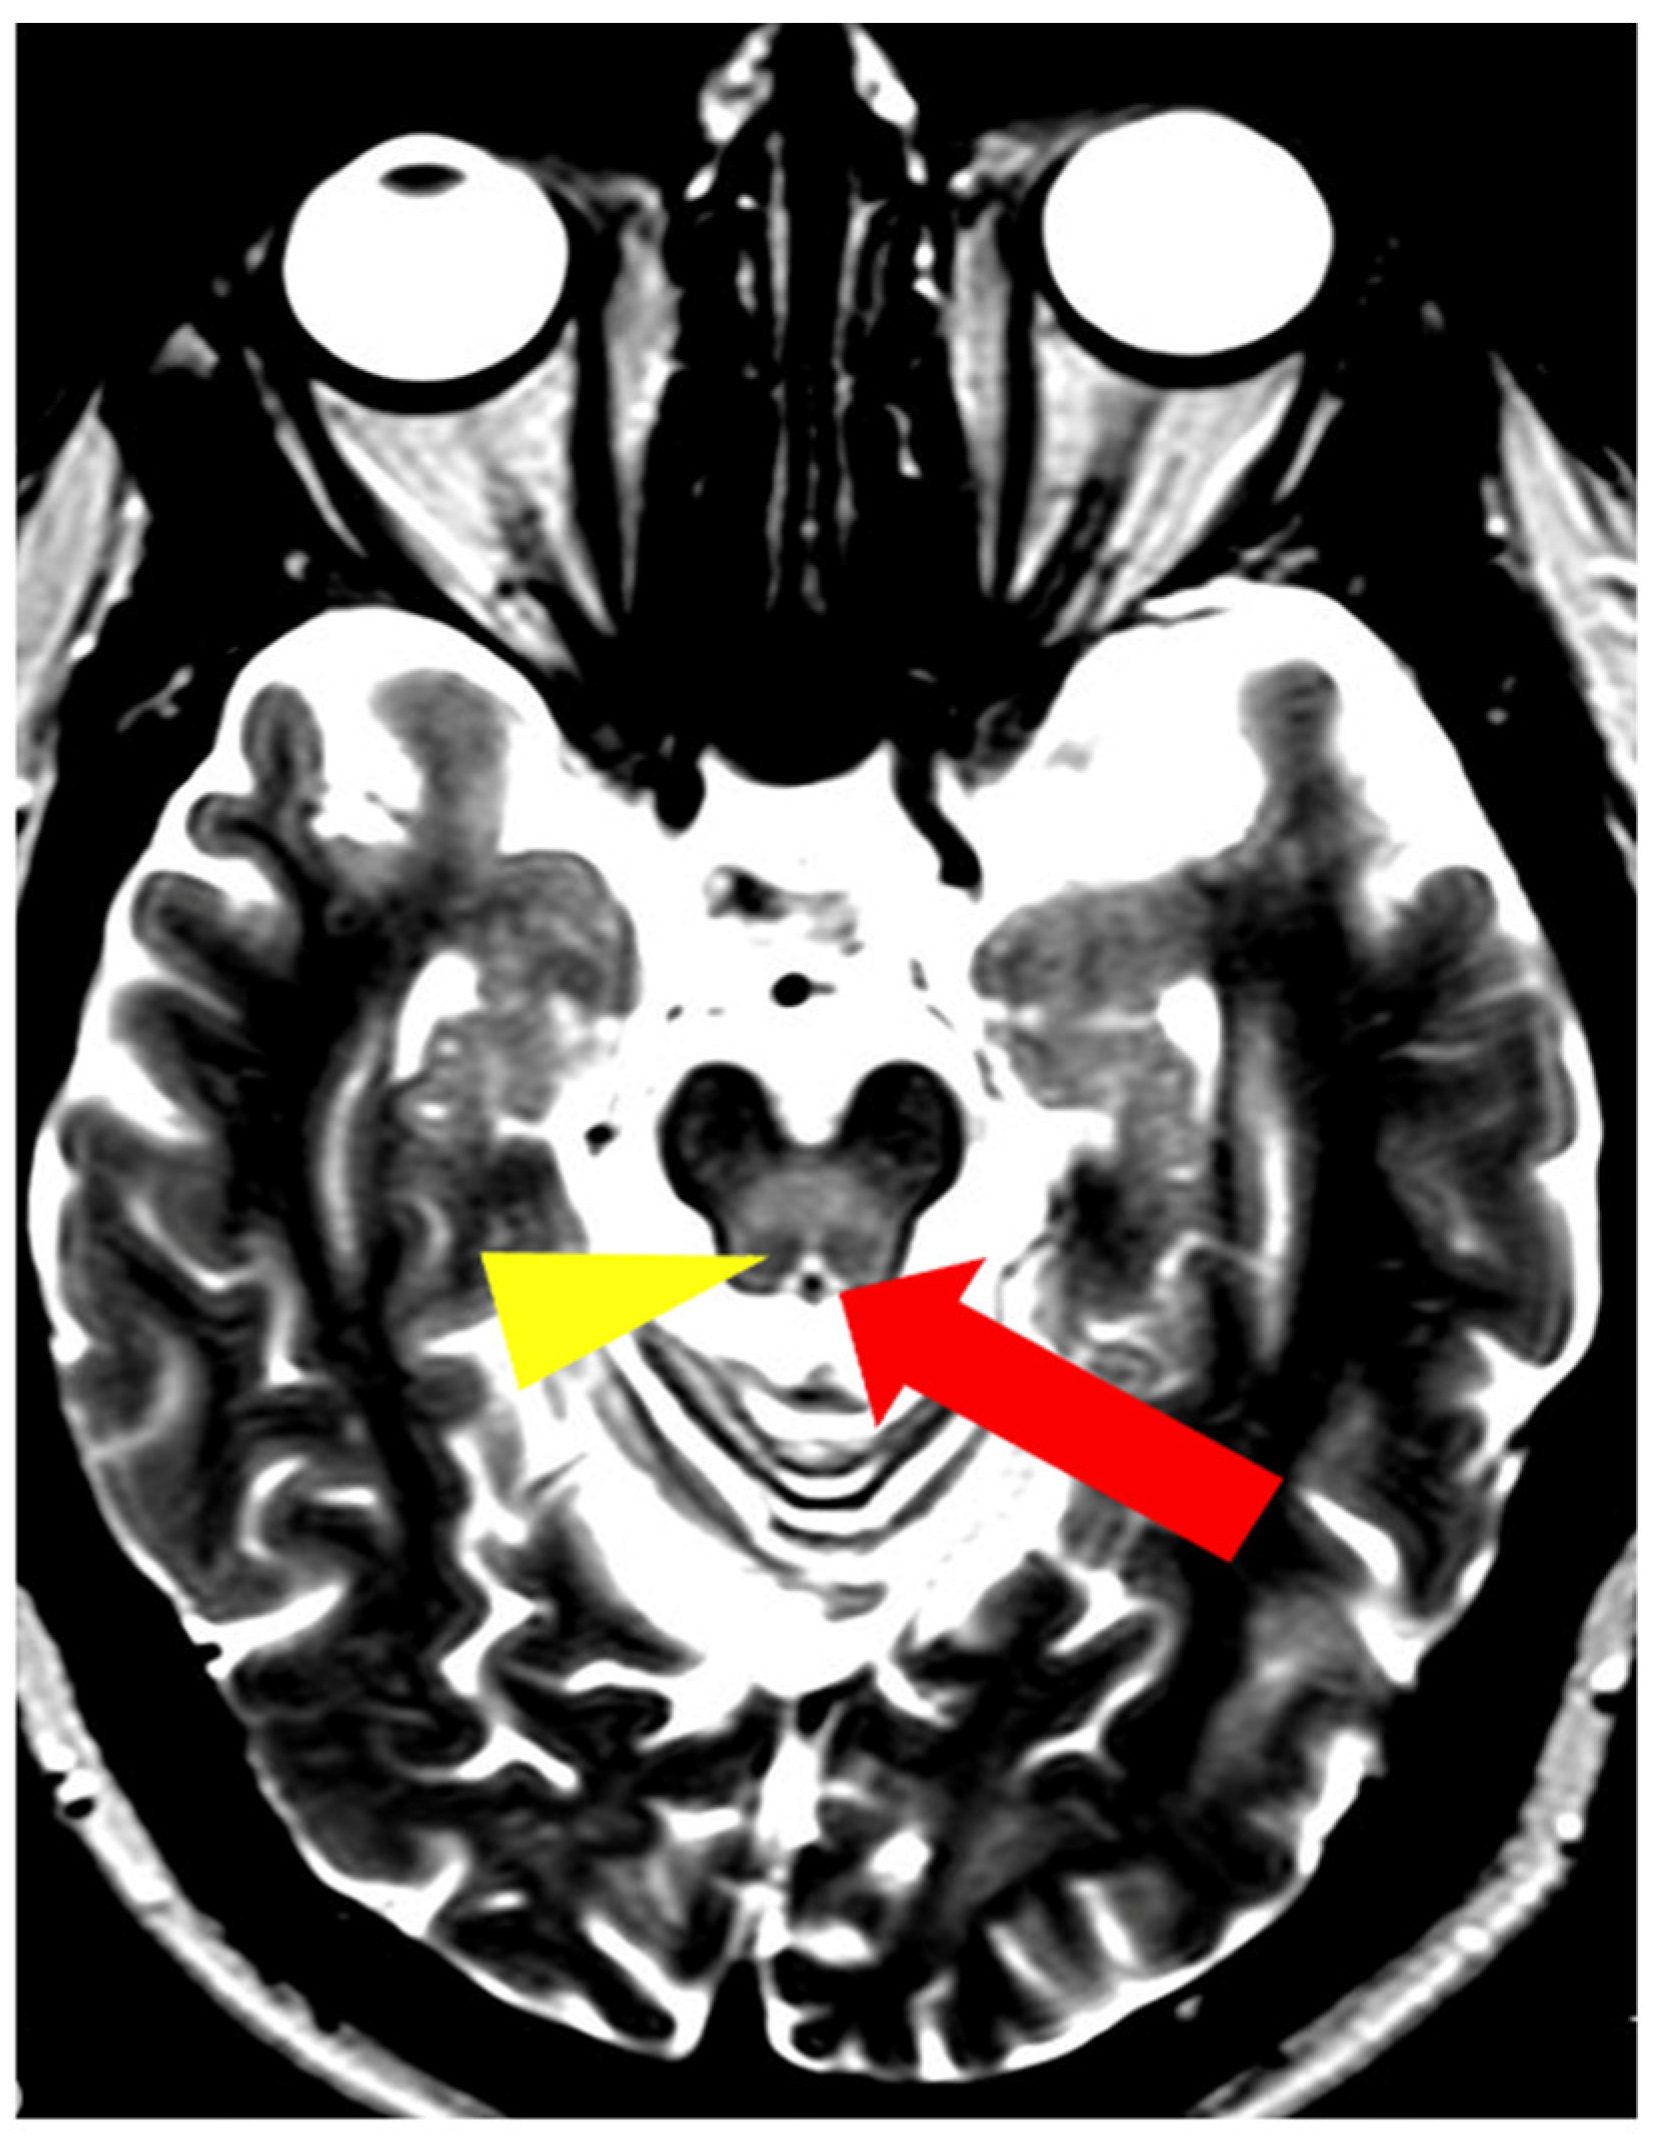

5. Neuroradiological Pathognomonic Signs of WD

- Hitoshi, S.; Iwata, M.; Yoshikawa, K. Mid-brain pathology of Wilson’s disease: MRI analysis of three cases. J. Neurol. Neurosurg. Psychiatry 1991, 54, 624–626. [Google Scholar] [CrossRef] [PubMed]

- George, U.; Varte, N.; Rathore, S.; Jain, V.; Goyal, S. “Split thalamus”: Internal medullary involvement in Wilson’s disease. Neurol. India 2010, 58, 680. [Google Scholar] [CrossRef] [PubMed]

- Sener, R.N. The claustrum on MRI: Normal anatomy, and the bright claustrum as a new sign in Wilson’s disease. Pediatr. Radiol. 1993, 23, 594–596. [Google Scholar] [CrossRef] [PubMed]

- Vella, S.; Grech, R. Highlighting an atypical cause of the Face of the Giant Panda sign. BJR Case Rep. 2018, 4, 20170046. [Google Scholar] [CrossRef] [PubMed]